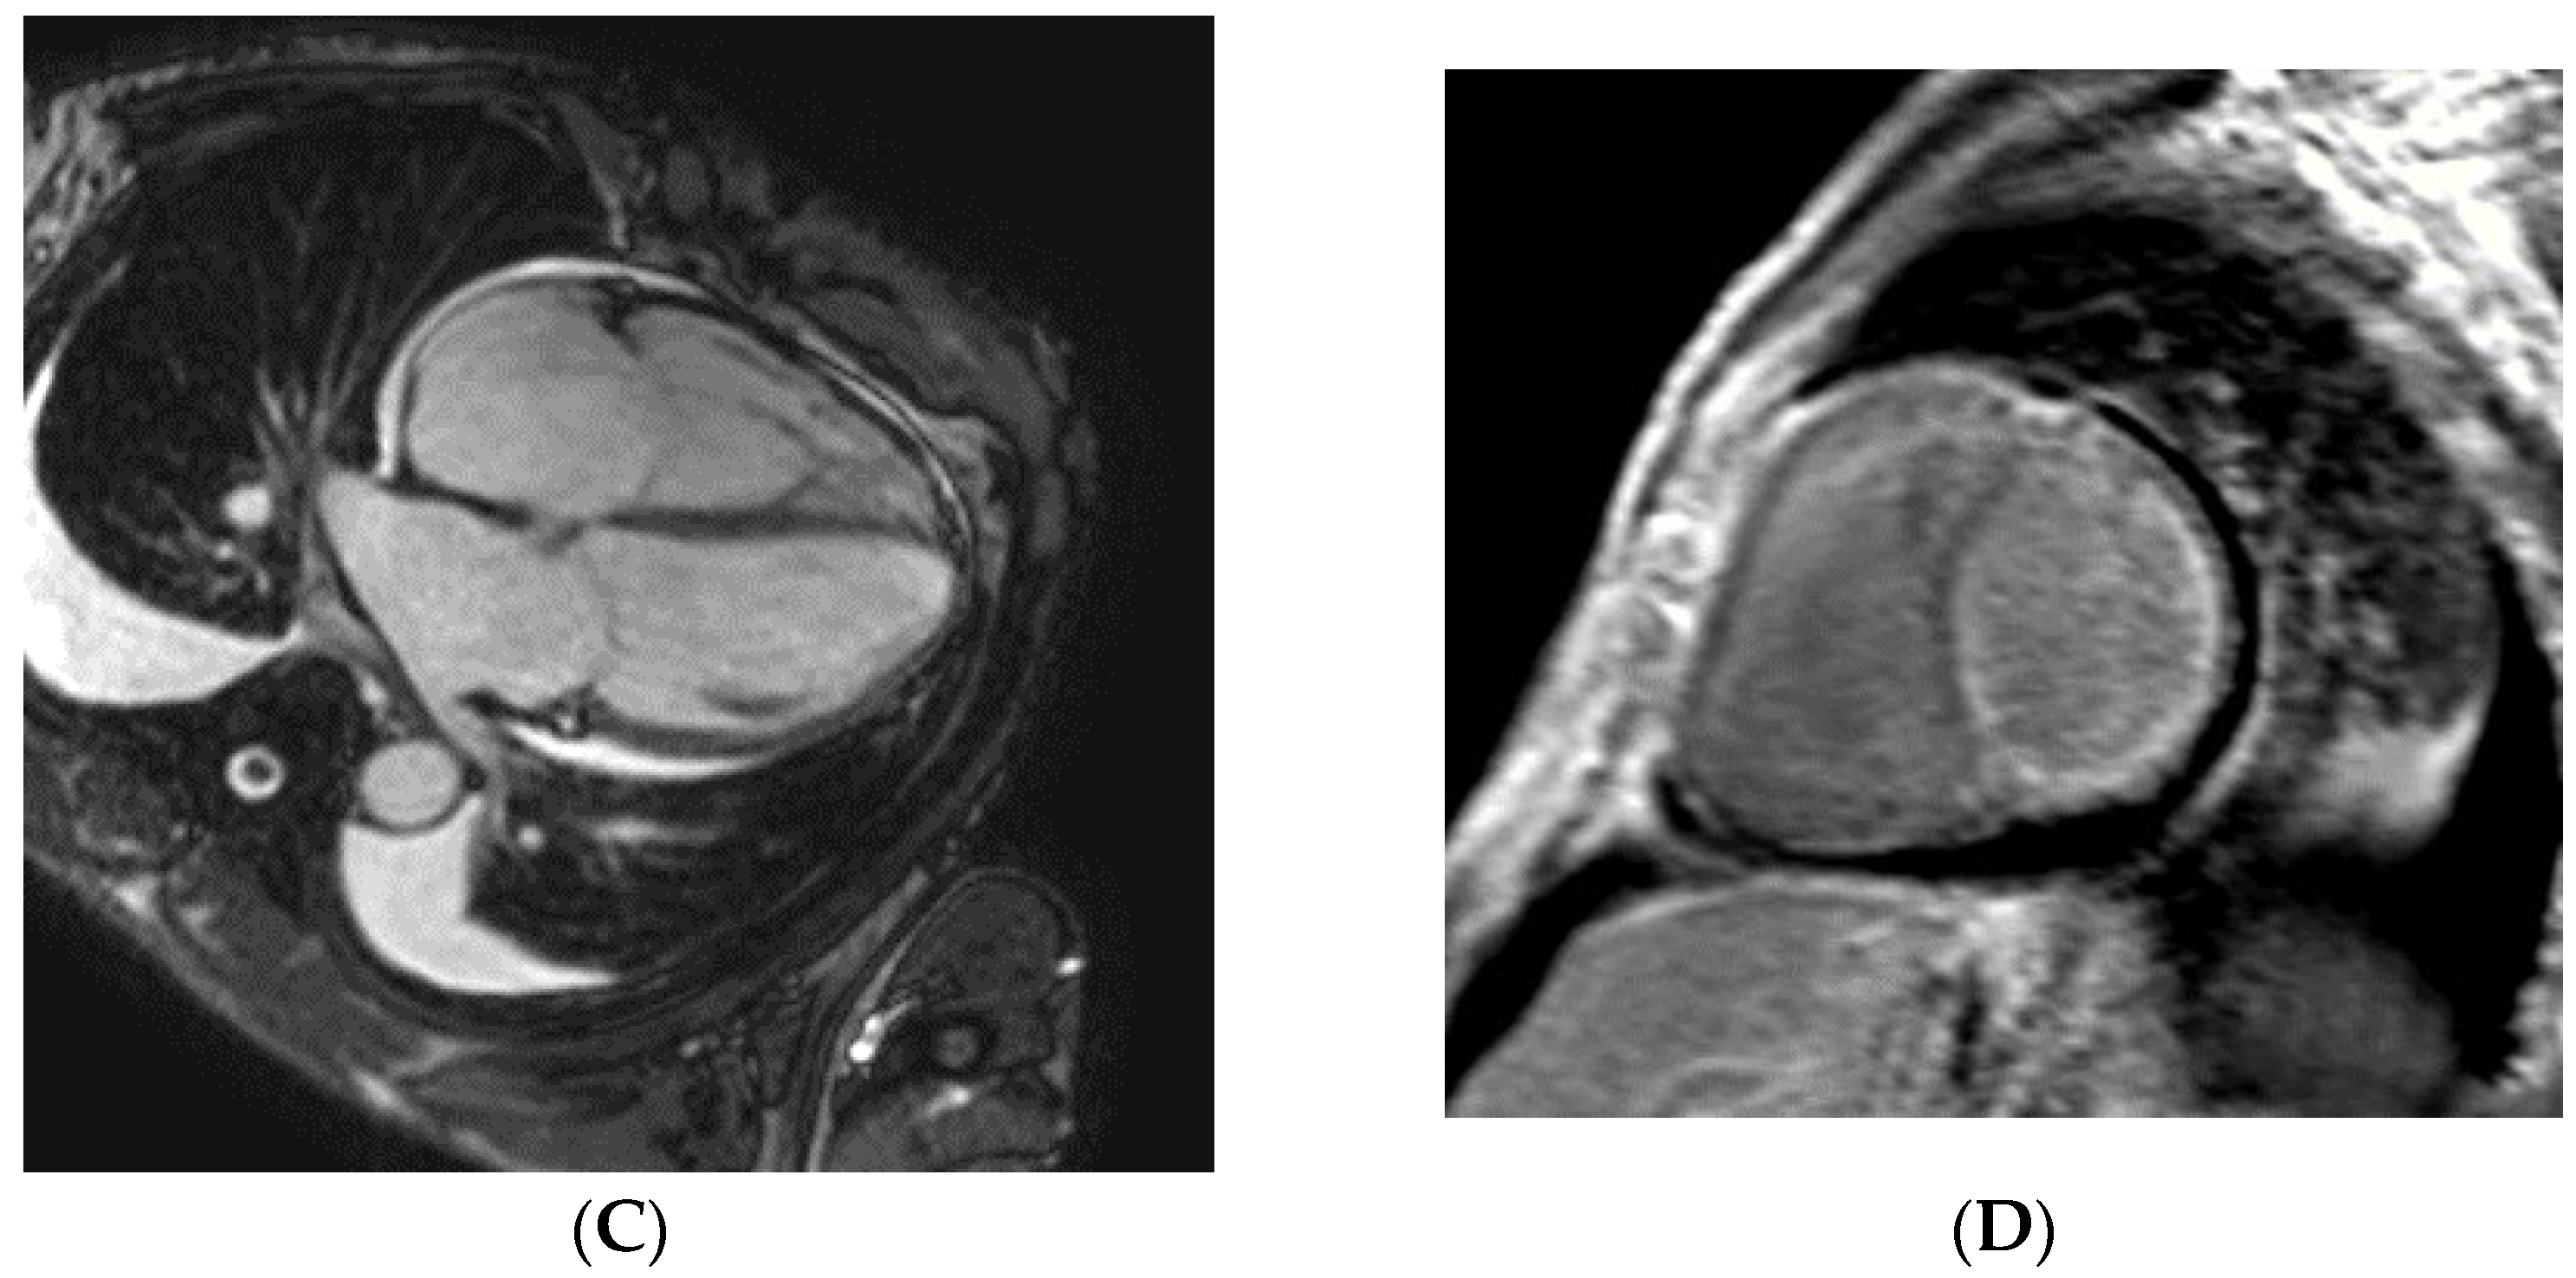

| Pt | Age at Diagnosis (Years) Sex of Patient | Left Ventricular Septal/Inferior/Average Wall Thickness (mm) EDV (mm)/ EF Measured with Echocardiography | E/e’ | Stage of Heart Failure According to NYHA at the Time of Diagnosis | NTproBNP (pg/mL) | Troponin T (ng/L) | GFR (mL/min/ 1.73 m2) | Organ from where the Biopsy Proved AL Amyloidosis | Result of CMR | Known PCD Before the Diagnosis of CA | Complaint, Symptom that Led to the Diagnosis of CA/Other Clinically Significant Organ Involvement |

|---|---|---|---|---|---|---|---|---|---|---|---|

| 1 | 65 male | 10/10/10 | 33.5 | IV | 6492 | 50 | 23 | rectum | typical for CA | No | heart failure/ polyneuropathy |

| 54/22 | |||||||||||

| 2 | 59 male | 10/10/10 43/56 | 8.95 | II | 2106 | 55 | 108 | heart | typical for CA | Yes | heart failure/ polyneuropathy |

| 3 | 52 male | 11/11/11 | 16 | III | 1537 | 42 | 80 | heart | typical for CA | No | heart failure/CTS, polyneuropathy |

| 42/63 | |||||||||||

| 4 | 75 female | 12/11/11.5 43/35 | 18.6 | III | 4311 | 96 | 112 | skin of eyelid | NP | No | heart failure/- |

| 5 | 59 female | 10/10/10 36/63 | 14 | I | 1436 | 69 | 26 | kidney | NP | Yes | screening for CA/ nephrotic syndrome |

| 6 | 72 female | 11/12/11.5 41/40 | 35.8 | IV | 6925 | 50 | 85 | abdominal fat | typical for CA | No | heart failure |

| 7 | 56 male | 9/9/9 42/53 | 13.9 | II | 573 | 32.9 | 113 | skin of eyelid, capsular ligament | LGE in atrial walls | Yes | screening for CA/ joint pain/ CTS |

| 8 | 58 female | 10/10/10 36/60 | 8.9 | I | 486 | 10 | 51 | kidney | not typical for CA | Yes | screening for CA/ polyneuropathy/ nephrotic syndrome |

| 9 | 82 female | 11/11/11 51/60 | 15.6 | II | 1717 | 8 | 51 | abdominal fat | not typical for CA | Yes | heart failure |